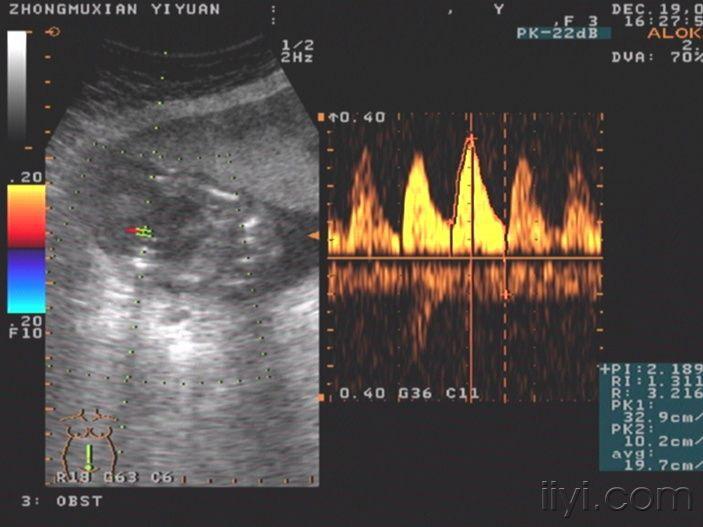

78柠檬征开放性脊柱裂中,97%胎儿在24周前有香蕉小脑征.

枣庄市妇幼保健院超声科诊断出一例胎儿开放性脊柱裂

柠檬头,脑积水,脊柱裂所以四维彩超现在已经成为检测胎儿健康的一大

柠檬头合并脊柱裂一例